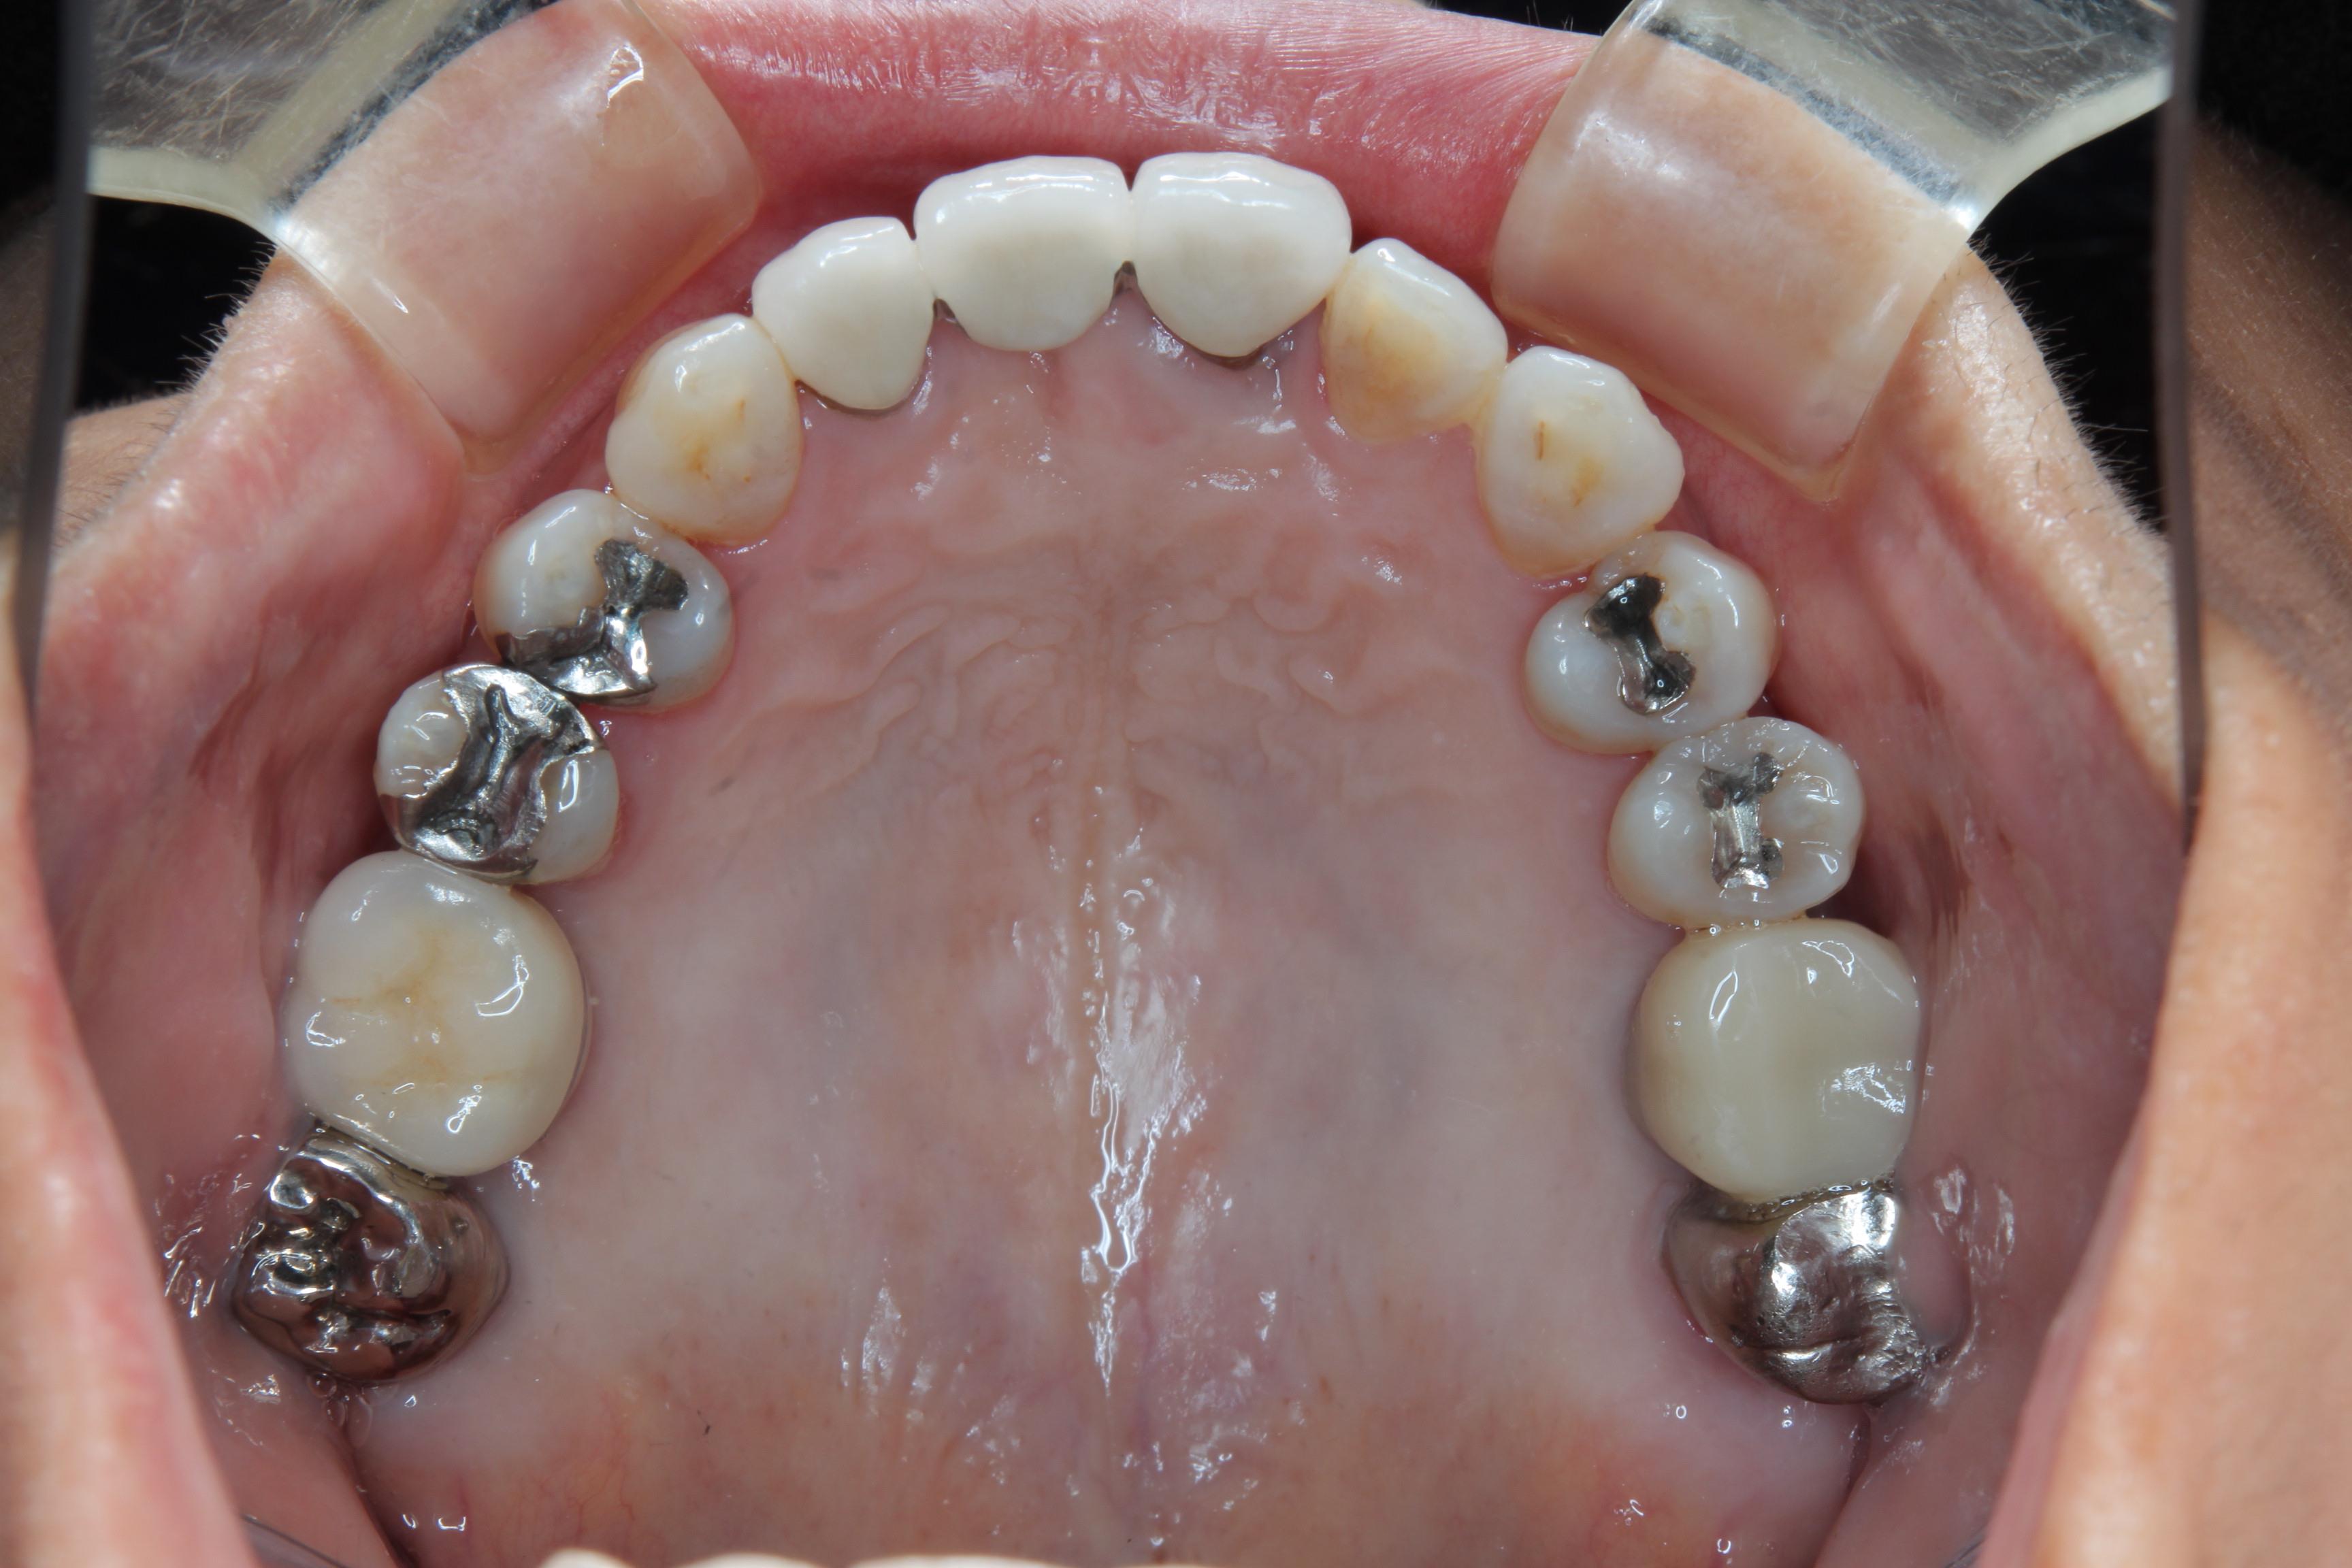

この患者さんは、大学病院勤務の時に先輩だった先生が、勤務していたクリニックで担当していた患者さんですが、

その先生が地方の実家に帰って開業するということで、右上(写真では向かって左)のインプラント治療とその後のメインテナンスの依頼で紹介していただいた方です。

右上の奥から2番目(銀色の被せものが入っている)の周囲の骨がほとんど無くなっており、抜歯せざるを得ない状態です。

インプラントと周囲の骨がインテグレーションするのを待って、2次手術を行い、最終的にインプラントにメタルセラミックスクラウンを装着しました。